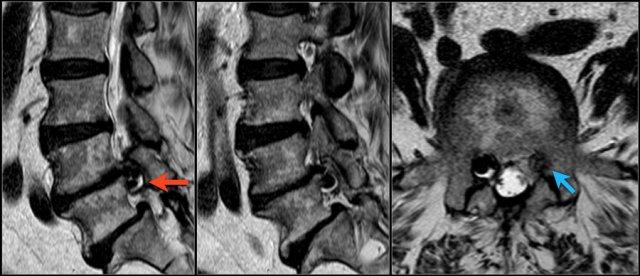

Các dấu hiệu bao gồm:

- Thoát vị đĩa đệm L3L4.

- Di trú lên phía trên.

- Chèn ép rễ thần kinh L3 trong lỗ liên hợp.

Cường độ tín hiệu của thoát vị đĩa đệm trên chuỗi xung T1W thường ở mức trung gian, trong khi trên chuỗi xung T2W có thể tăng tín hiệu trong trường hợp nhân nhầy thoát vị mới hoặc giảm tín hiệu trong trường hợp thoát vị cũ hơn.

Hình ảnh thoát vị tăng tín hiệu (mũi tên vàng trên ảnh cắt ngang) trượt qua vết rách vòng sợi và chèn ép rễ thần kinh L5 bên trái (mũi tên xanh dương).